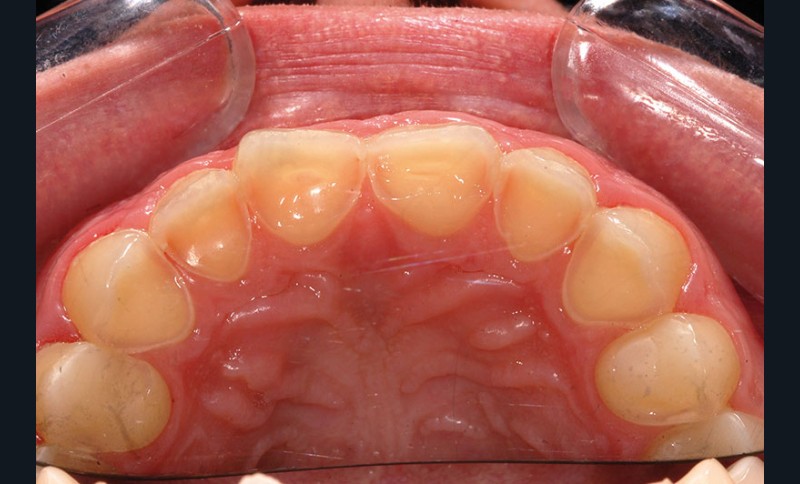

À l’examen clinique, les dents, principalement antérieures, présentent des pertes de substances importantes de classe V selon la classification ACE (Anterior Clinical Erosive Classification) de Vailati [1] (fig. 1 à 6).

Les examens complémentaires, dont un sondage parodontal, montrent l’absence de maladie parodontale (fig. 7).

Le parodonte marginal est de type 1 selon la classification de Maynard et Wilson [2]. On note également la présence d’une grande quantité de gencive attachée située apicalement par rapport aux lésions dentaires.